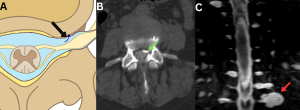

Fig 13: Figure A: Illustration demonstrating a spinal ventral dural tear caused by a calcified discal spur (straight black arrow). Black curved arrows indicate the route of cerebrospinal fluid (CSF) leakage into the epidural space.

Figure B: Sagittal bone-window CT image of the thoracic spine showing a discogenic spur (red arrow).

Figure C: Sagittal T2-weighted MR image of the thoracic spine demonstrating a T2 hyperintense anterior spinal epidural collection (SLEC) (green arrow).